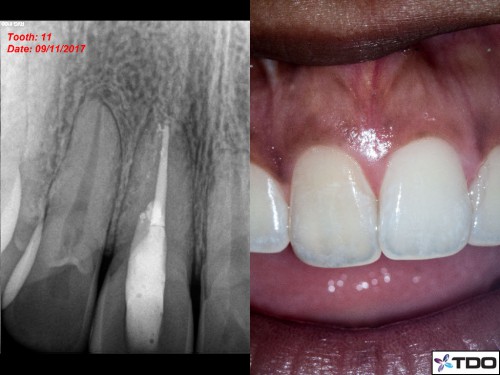

23 YF presented with pain and clinical signs of GP inside the buccal aspect of the gingiva around tooth #11 (FDI). The scan shows the buccal perforation with two GP points and an apical finding. Initially we removed all GP fragments internally and repaired the internal aspect of the perforation with SDR and interim CaOH was placed into the true canal. Second visit, the patient was asymptomatic and the surgical phase involved repairing the perforation defect with Geristore. The RCT was then completed and the access was closed with resin. Patient was very happy with the aesthetics at the follow-up and no- probing was evident at the perforation site through the buccal marginal gingiva. I hope this turns out well long-term.